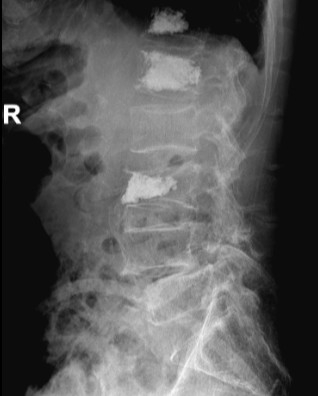

术前

骨质疏松胸腰椎压缩性骨折多发生在老年人,均在骨质疏松基础上发生,有时并没有明显外伤病史,因骨质疏松甚至咳嗽或打喷嚏都可能引起骨折。骨折后因疼痛较剧烈,翻身都较困难,病人较痛苦,严重影响患者生活质量,目前治疗上均采用微创手术“经皮穿刺椎体成形术”,术后马上减轻疼痛9成以上,手术效果非常好,第二天就能下地。

李伯随即转入骨科治疗,张勇华副院长、骨科主任带领的骨科团队经讨论,详细制定手术方案并征得家属同意,决定尽快为李伯进行“经皮穿刺椎体成形术”,手术由李竖飞、林勇医生完成,手术顺利,术后2小时腰背部疼痛明显缓解,第二天李伯便可戴腰围下地行走,很快顺利出院,精神状态及身体各方面恢复良好。00: